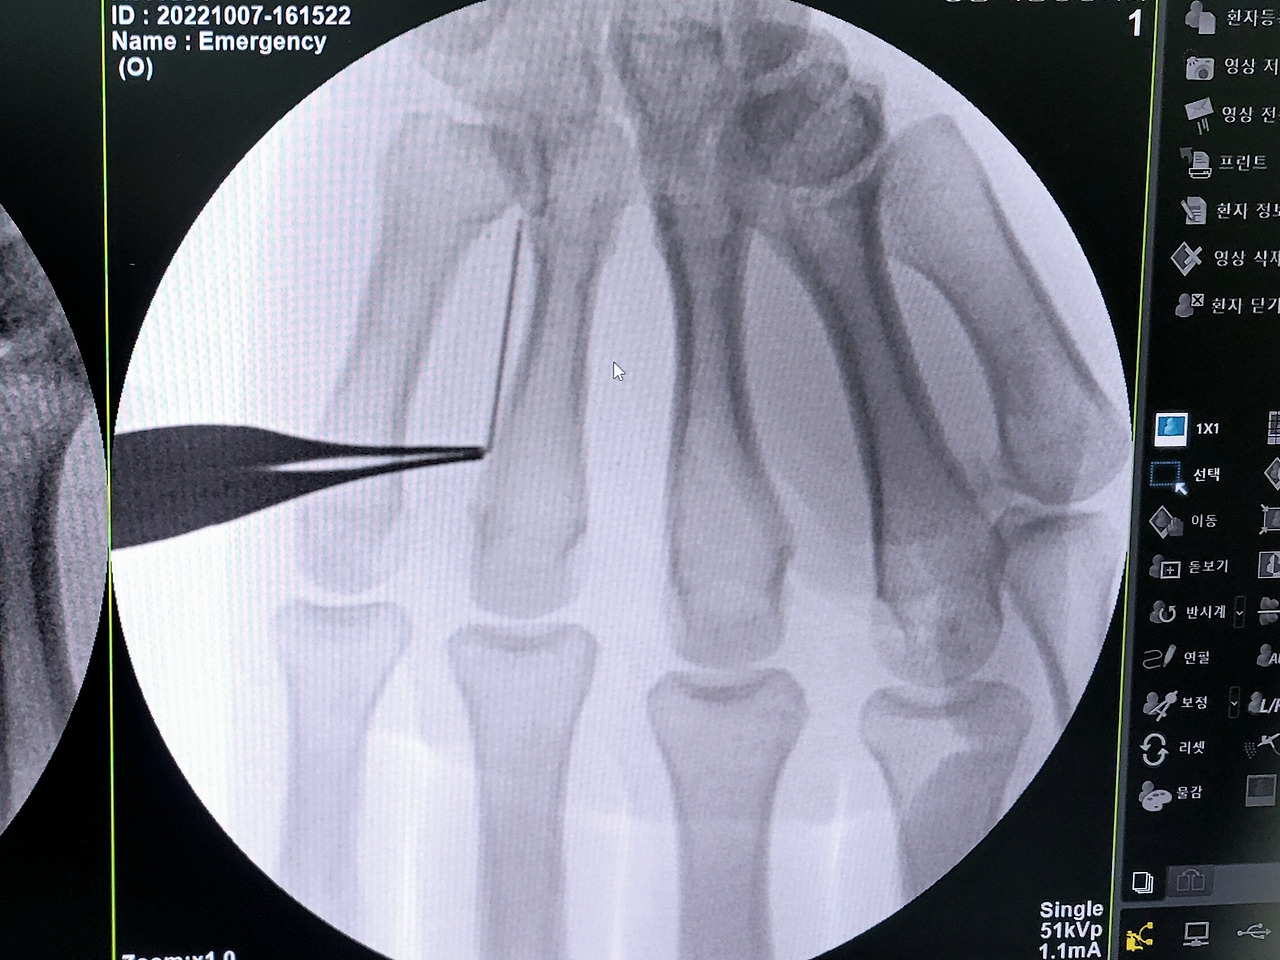

엑스레이로 촬영해가며 바늘 위치를 찾는 중

무려 바늘이 손바닥 안으로 깊숙이 들어가버려 부득이하게 손바닥을 가르고 꺼냈다.